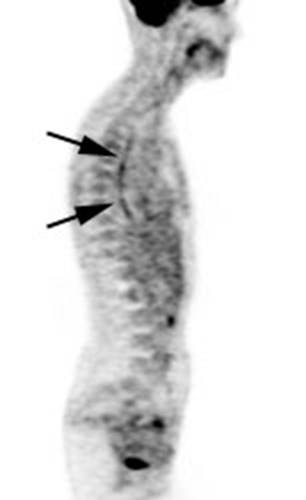

Figure 21 - Marrow activity: The images below are from

two separate patients each showing mild FDG accumulation within the vertebral

bodies.

Figure 22 - Growth colony effect: The patient shown below

had received growth colony stimulating factor (GCSF). Note the extensive

increased marrow activity. Note increased splenic activity also seen as a result of GCSF therapy.